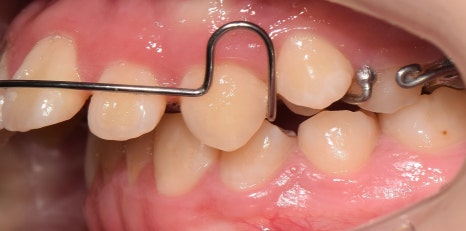

교정의 한 분야인,

헤드기어 =head gear는

1) 입안에 끼는 장치

2) 머리에 쓰는 밴드

3) 이들을 연결하는 탄성 모듈로 구성되어 있으며,

위 사진처럼,

위턱뼈가 앞으로 돌출되었을 때

상악 성장을 막기 위해 사용되고 있습니다.

즉, 위턱뼈가

앞으로 자라지 못하도록

뒤로 당겨주는 역할을 하게 되는데요.

가철식 장치 및 헤드기어 착용